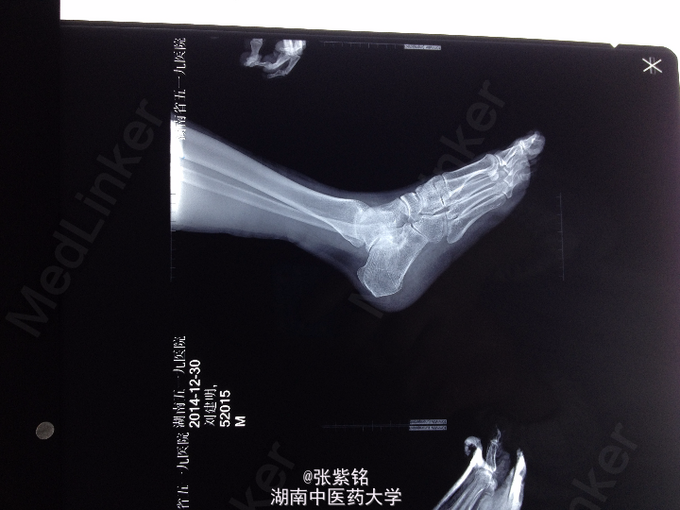

查体:左足部肿胀明显,可见大面积皮下青紫瘀斑,压痛明显,尤以足跟部为甚,左足跟部可扪及明显骨擦音,足踝关节主动活动受限,被动活动疼痛明显加重,左足背动脉搏动可扪及,伤肢血运感觉可。 辅查:左足正斜位片示:左跟骨骨折。 左足CT平扫+三维重建:左跟骨骨质连续性中断,可见多发骨折线,骨折端对位对线不良,并可见多块碎骨片,骨折线累积关节面,左足软组织明显肿胀;左跟骨粉碎性骨折。